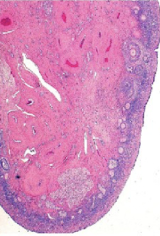

What organ is in the image provided and what phase of the estrous cycle is it in?

ovary in estrus